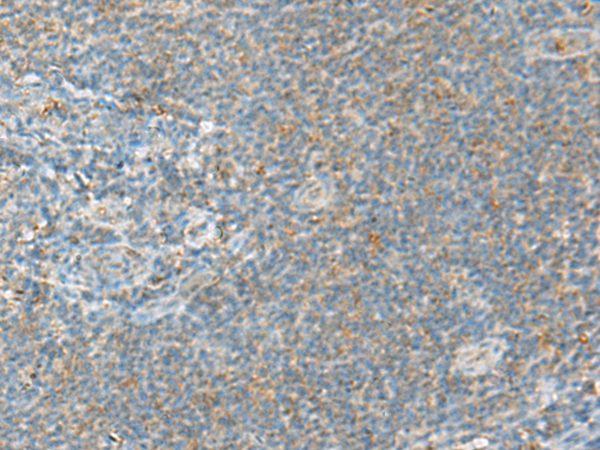

分类: 科研抗体货号: P13548别名: IHABP4; IHABP-4; Ki-1/57; SERBP1L应用: IHC反应种属: Human, Mouse, Rat